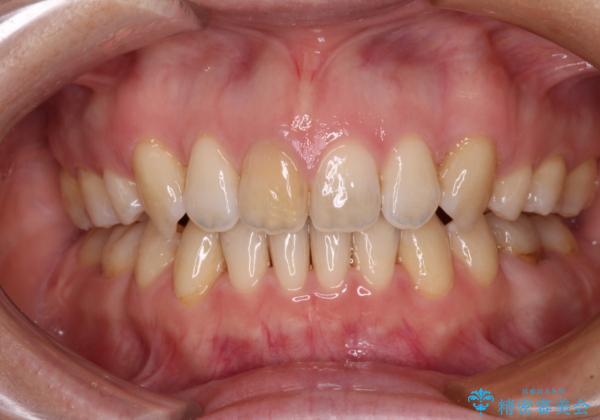

抜歯矯正で閉じにくかった口を閉じやすく改善

- 上の前歯の飛び出した感じを改善したいとのことで来院された患者様です。

上顎左右第一小臼歯2本、下顎左右第二小臼歯2本を抜歯し、ワイヤー装置にて口元を引っ込めるよう矯正治療を行うこととしました。

上下の前歯に隙間が空くほど上顎前歯が前に飛び出していましたが、抜歯矯正により上下前歯がぴったりと付くほど口元を引っ込めることができました。